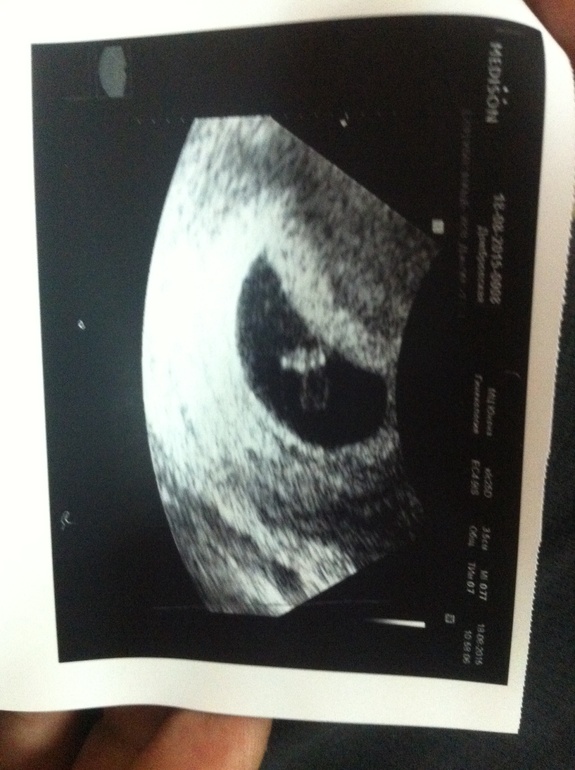

Как я счастлива))

Беременность- 1 триместр ( только до 10 недель)